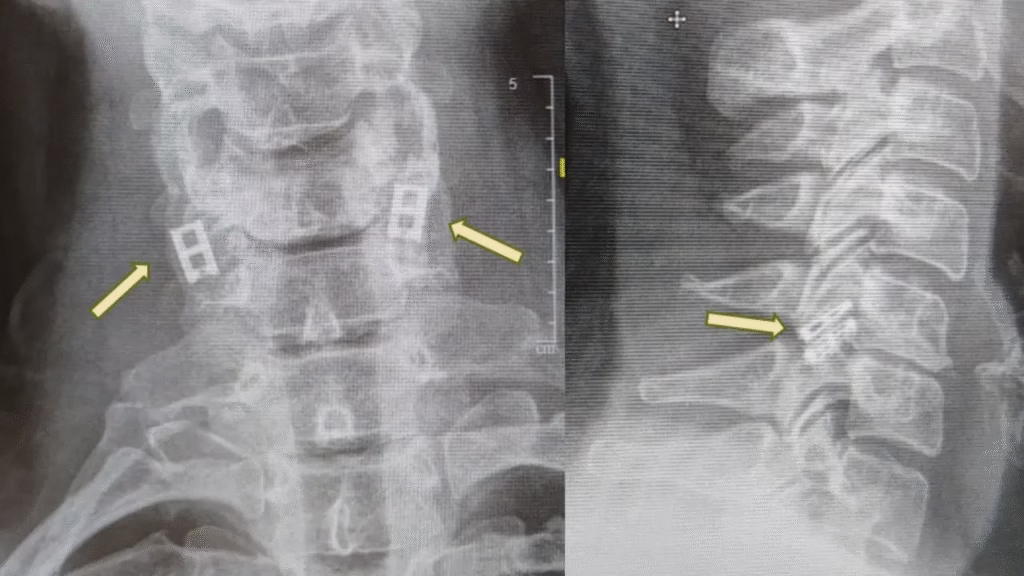

The spinal cord acts like an electrical cable, carrying signals from the brain to the body. When it’s cut, the connection is lost, and the patient is paralyzed below the injury, explained Professor Tal Dvir, who leads the project at Tel Aviv University’s Sagol Center for Regenerative Biotechnology. Dvir is also the chief scientist at Matricelf, the biotech company behind the new therapy.

Unlike other tissues, the spinal cord does not regenerate naturally. Scar tissue that forms after an injury makes recovery even more difficult. The new approach seeks to replace the damaged section with lab-grown tissue that can reconnect healthy nerves above and below the injury. In animal studies, paralyzed rats treated with this method regained the ability to walk.

Here’s how the procedure works: Doctors take blood cells from the patient and reprogram them into stem-like cells, which can become any cell type. Fat tissue is also collected to create a gel-like scaffold. Together, these materials are used to grow a personalized spinal cord structure in the lab. Once ready, the engineered tissue is implanted to replace the scarred area, reconnecting the nervous system.